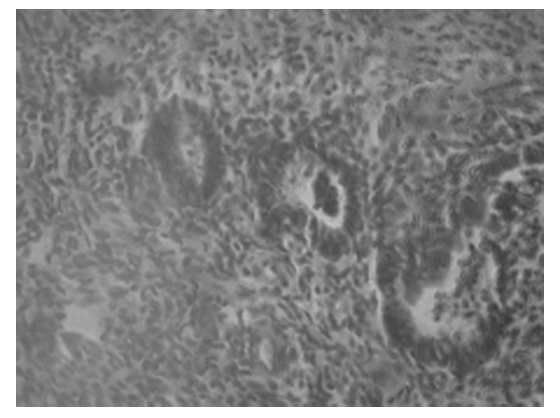

При гистологическом исследовании биоптатов яичников (диагностическая лапароскопия в 3 случаях) была выявлена выраженная диффузная лимфоидная инфильтрация в корковом слое интенсивностью в 3 балла и очаговая – вокруг структурных его образований в 3 балла, при сохранении примордиальных фолликулов, что расценивается как аутоиммунное поражение яичников (рис. 4). У этих больных был установлен и повышенный уровень антиовариальных антител (табл. 3), что подтверждает вышесказанное.